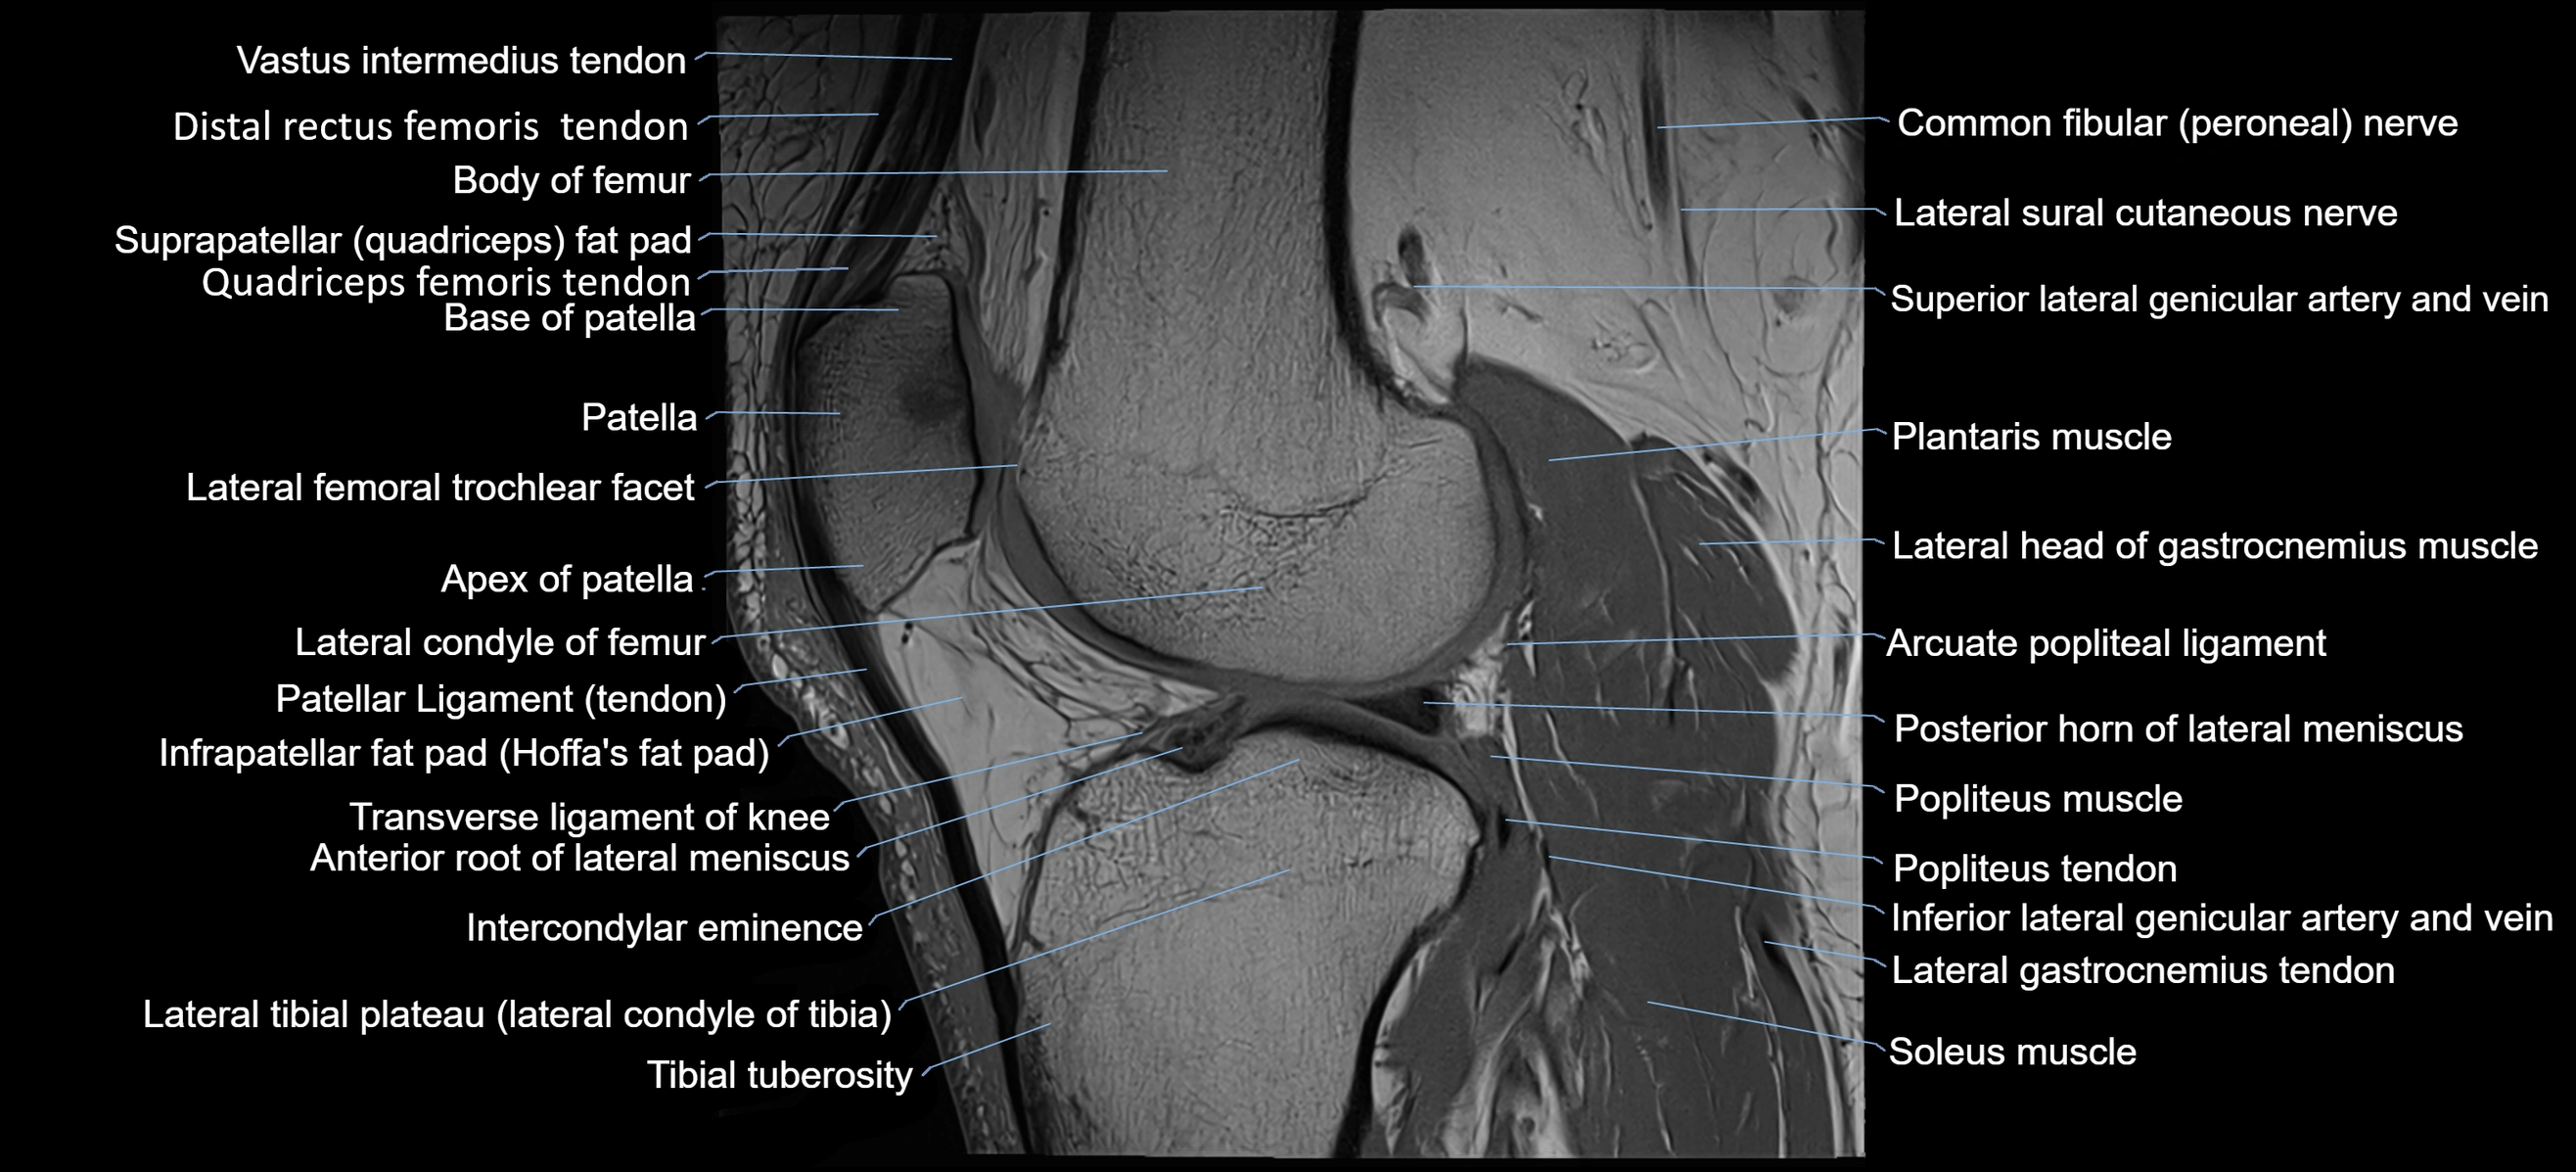

- Anterior root of lateral meniscus

- Arcuate popliteal ligament

- Body of femur

- Common fibular nerve

- Distal rectus femoris tendon

- Distal vastus intermedius tendon

- Head of fibula

- Inferior lateral genicular artery

- Inferior lateral genicular vein

- Infrapatellar fat pad

- Intercondylar eminence

- Lateral condyle of femur

- Lateral gastrocnemius tendon

- Lateral head of gastrocnemius muscle

- Lateral sural cutaneous nerve

- Lateral tibial plateau

- Patellar tendon (patellar ligament)

- Plantaris muscle

- Popliteus muscle

- Popliteus tendon

- Posterior horn of lateral meniscus

- Soleus muscle

- Suprapatellar fat pad

- Tibial tuberosity

- Transverse ligament of knee